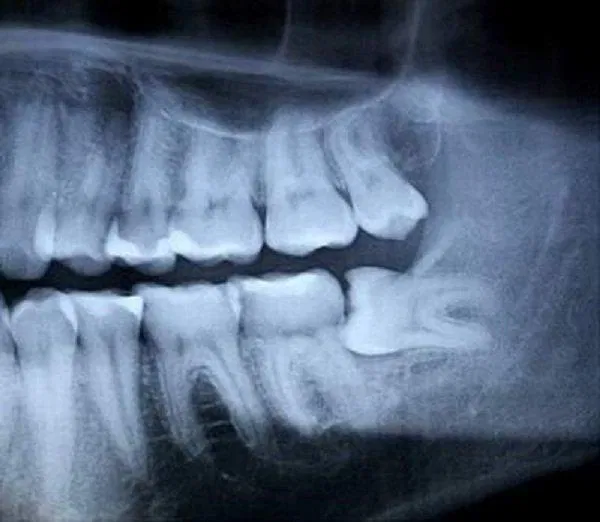

Trong những buổi khám răng định kỳ, nha sĩ có thể cho bạn chụp phim X quang hàm răng để kiểm tra vị trí và cách sắp xếp của răng khôn khi chúng chưa nhô lên khỏi hàm.

Ngoài những lý do kể trên, trong các lần khám răng định kỳ nha sĩ có thể quan sát khung xương hàm, đánh giá các răng của bạn và chụp phim X quang để quyết định xem có cần nhổ bỏ răng khôn hay không.